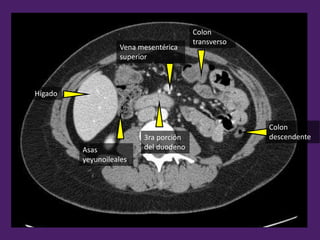

Lóbulo

derecho

del hígado

Vena

cava

inferior

3ra porción

del duodeno

Vena mesentérica

superior

Colon

transverso

descendente

Asas

yeyunoileales

Hígado